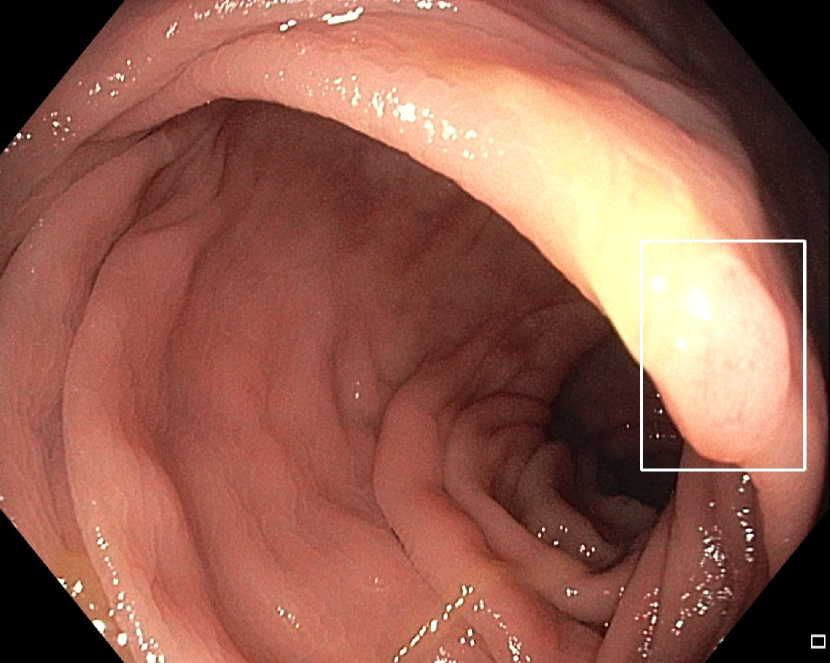

Refer to caption

(a)

Figure 7: Sample images from the testing dataset, with results from the best performing model. White boxes are the ground truth annotations, blue ellipses are the model predictions. In the first row, examples of false negative polyps are shown: (7(a)) a small and distant polyp, (7(b)) a polyp partially covered by water/bubbles, (7(c)) a polyp framed in blue light, (7(d)) a large polyp near the image boundary and overexposed. In the second row, examples of false positive detections are shown: (7(e)) the model activates on a artifact due to stain and motion blur, (7(f)) the model activates on a solid residue, (7(g)) the model activates on an area of the colonic mucosa that is not well inflated, (7(h)) the model activates on a dark and distant area of the colonic mucosa whose shape is similar to a polyp.

Finally, in Figure 7, we display examples of false negatives and false positives from the test set, generated by the best performing model. To visually assess the performance on a whole video, we have uploaded a 60-minute colonoscopy video featuring 6 polyps, the longest in our test set, at https://figshare.com/s/fbb0834a21082984336c (with predictions marked in cyan and ground truth boxes in white). The image examples illustrate how the model struggles with small, occluded, or poorly imaged polyps, and generates false positives in areas that visually resemble polyps, often due to motion or suboptimal imaging. These observations persist throughout the entire video analysis, highlighting the importance of minimizing false positives throughout the entire procedure while maintaining high polyp recall.